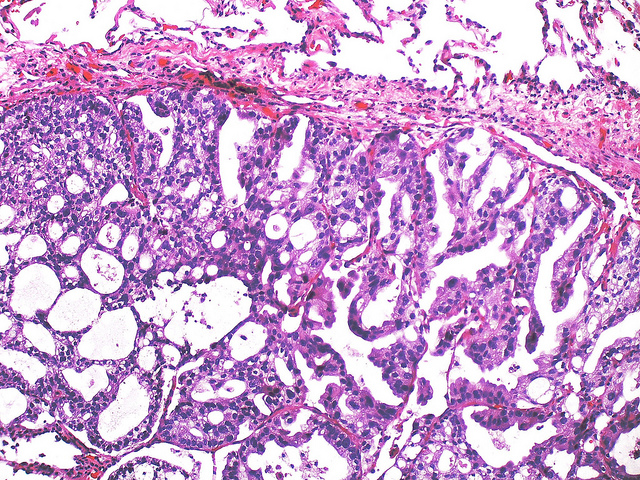

Inflammation, parasites, and cancer have long been interconnected. We have included some images of interest showing some of the known human blood-dwelling parasites, Schistosoma induced cancer, and prostate cancer pathology. For more research supporting links between cancer and infections we suggest these publications:Chronic Bacterial Infections and Cancer Risk Colorectal Cancer and Schistosoma Schistosoma Prostate Case Report #1 Schistosoma Prostate Case Report #2 Parasitic Infection and Cancer

Metastatic prostate adenocarcinoma (Flickr user Yale Rosen)